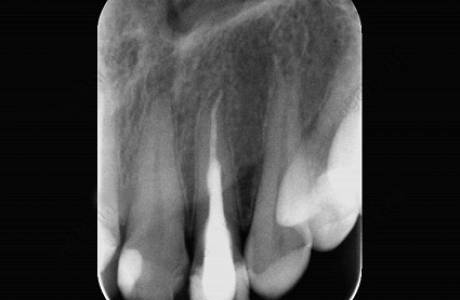

До лечения

Пациентка обратилась к врачу с острой болью. После изучения прицельного снимка обнаружилась резорбция (разрушение) корня с двумя гранулемами (участками воспаленной ткани).

После лечения

Как правило, такие зубы идут на удаление. В данном случае врач решила сохранить зуб. Было проведено эндодонтическое лечение, которое закончилось через несколько недель. Зуб пациентки сохранен.